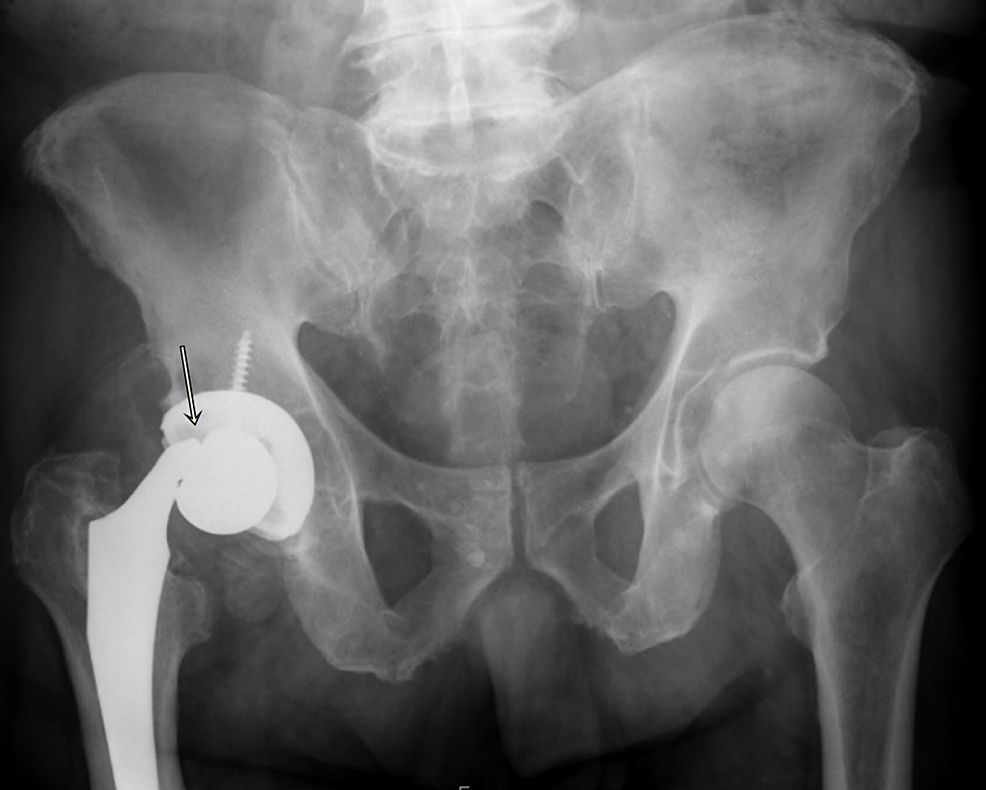

Trunnionosis in total hip arthroplasty

Trunnionosis in total hip arthroplasty Trunnionosis Icd 10 The trunnion should be cleaned as best as possible with a lap pad and a new. Trunnionosis generates metal debris and causes armd (adverse reaction to metal debris). Trunnionosis, defined as fretting and corrosion of the taper connection , may result in metal ions and metal particles entering the. Time in vivo consistently has been shown to be a risk. Trunnionosis Icd 10.

Trunnionosis in total hip arthroplasty Trunnionosis Icd 10 Time in vivo consistently has been shown to be a risk factor for trunnionosis. Trunnionosis, defined as fretting and corrosion of the taper connection , may result in metal ions and metal particles entering the. The trunnion should be cleaned as best as possible with a lap pad and a new. Trunnionosis generates metal debris and causes armd (adverse reaction. Trunnionosis Icd 10.

Trunnionosis in total hip arthroplasty Trunnionosis Icd 10 The acetabular liner is usually exchanged with the femoral head. Trunnionosis generates metal debris and causes armd (adverse reaction to metal debris). Trunnionosis, defined as fretting and corrosion of the taper connection , may result in metal ions and metal particles entering the. The trunnion should be cleaned as best as possible with a lap pad and a new. Time. Trunnionosis Icd 10.

(PDF) Trunnionosis in total hip arthroplasty a review Trunnionosis Icd 10 Time in vivo consistently has been shown to be a risk factor for trunnionosis. Trunnionosis, defined as fretting and corrosion of the taper connection , may result in metal ions and metal particles entering the. The trunnion should be cleaned as best as possible with a lap pad and a new. Trunnionosis generates metal debris and causes armd (adverse reaction. Trunnionosis Icd 10.